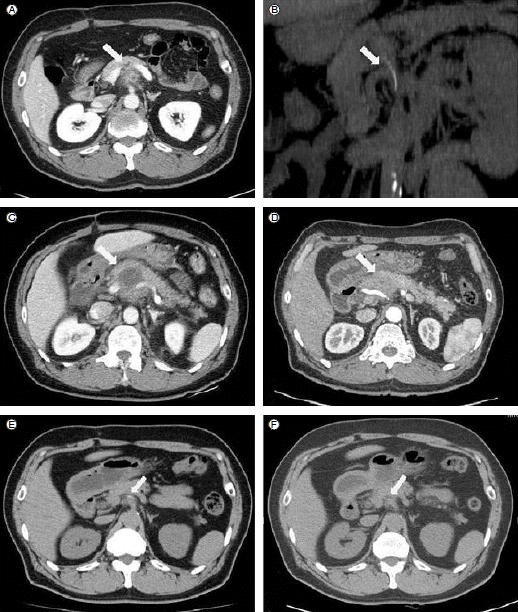

Figure 3.

In the second case, on admission, an outside CT scan revealed a pancreatic and retroperitoneal mass (A) and a high-density foreign body (B). On hospital day (HD) 4, the pancreatic mass had rapidly increased in extent (C). On HD 33, the pancreatic mass had almost disappeared (D). The foreign body remained, but there was no evidence of recurrence of abscess at 1 month (E) and 7 months (F) after discharge.